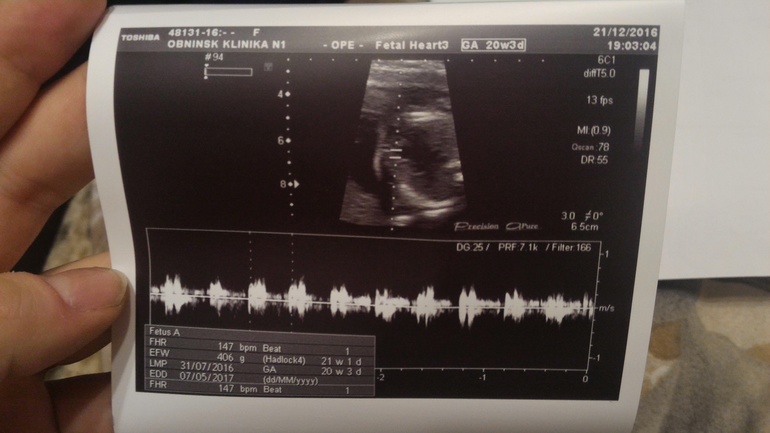

Сегодня 20 недель начались с похода на скрининг))) Нам там подтвердили сынульку, все с нами ттт хорошо, отклонений не выявлено по узи ставят 20+5 неделек) БПР -49мм , написали один живой плод в головном предлежании, плацента расположена по передней и задней стенкам левому ребру, лежим мы поперек маминого животика и я это прекрасно чувствую, буянит сын) головка справа,попка слева ))) Кол-во вод в норме шейка матки 39 мм)